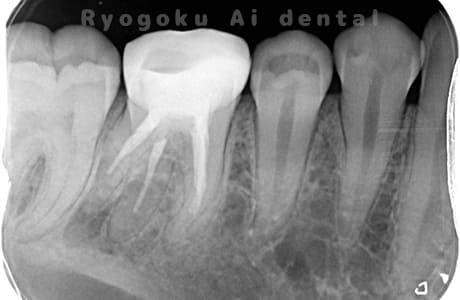

- 原因

- 慢性根尖性歯周炎

- 治療期間

- 3ヶ月

- 治療内容

- マイクロエンド

- 治療費用

- 121,000円

噛むと痛みが出る、とのことで来院した患者様です。他院での根管治療を終えてましたが、根尖病変を認めるため、マイクロエンドを行いました。